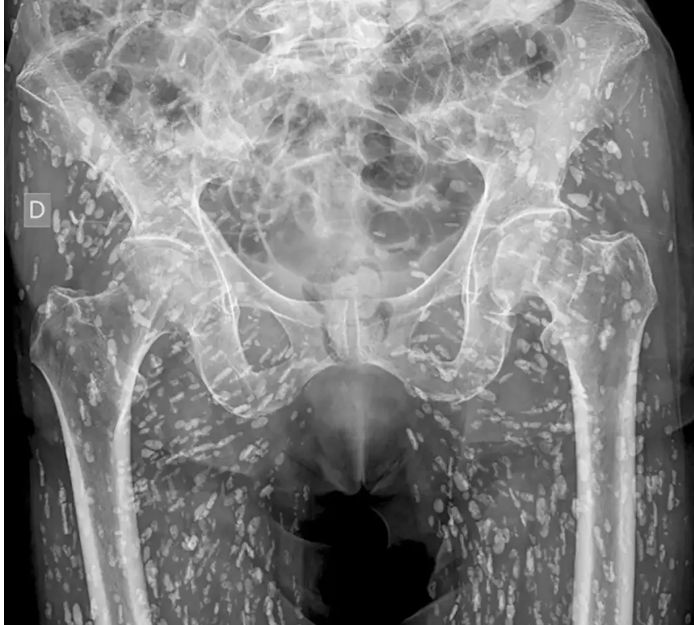

[서울=뉴시스]엉덩이뼈 골절로 촬영한 엑스레이에서 엉덩이와 다리 부위에 수백 개의 기생충 알이 발견된 남성의 충격적인 사연이 전해졌다.(사진=뉴욕포스트) *재판매 및 DB 금지

사진 속에는 엉덩이와 다리 근육 부위에 수백 개의 기생충 알이 석회화된 모습이 선명하게 드러나 있었다.

갈리 박사에 따르면, 이 남성은 돼지 촌충(Taenia solium)의 유충 낭종으로 발생하는 낭미충증(cysticercosis)에 감염된 상태였다. 덜 익히거나 날것 상태의 돼지고기를 섭취한 것이 원인으로 밝혀졌다.

갈리 박사는 이 환자의 낭종이 골반과 다리의 근육 및 부드러운 조직에 침투해 석회화됐다고 설명했다. 석회화된 낭종은 엑스레이에서 흔히 쌀알 모양으로 나타난다.